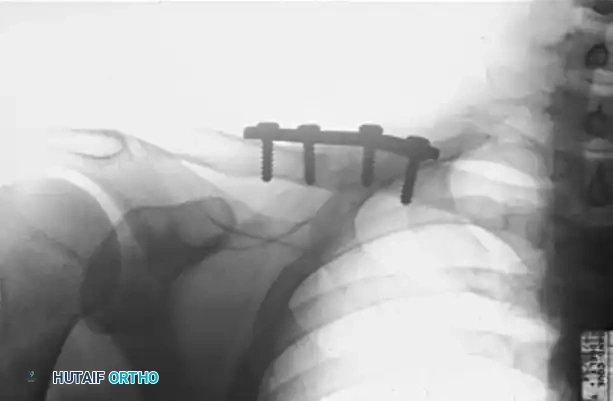

Figure A: Preoperative radiograph demonstrating a hypervascular nonunion of the clavicle. The patient presented with severe pain and instability 1.5 years following the initial fracture, exacerbated by a recent fall.

Figure B: Postoperative radiograph at 2.5 months demonstrating solid osseous union following aggressive decortication, application of a superior compression plate, and autologous bone grafting.